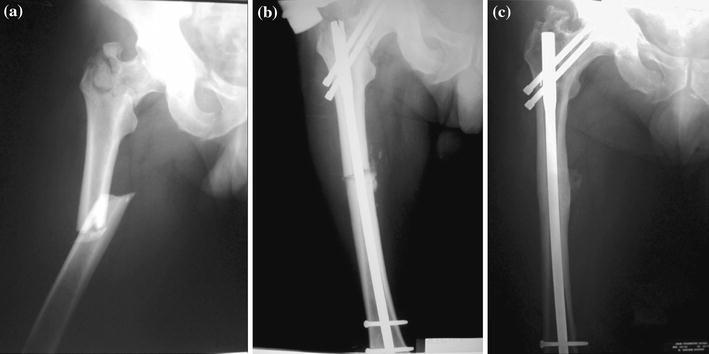

The mean HHS was 85 (range, 78–92). Range of motion for the hip joint was normal in all the patients. Knee flexion averaged 120° (range, 105–130). The two patients with the associated patellar fractures had the least knee flexion. Two patients, one with peroneal nerve palsy and another with a contralateral pilon fracture, reported slight limping. Two patients reported occasional pain that did not affect their everyday activities. All the patients returned to their pre-injury activity level and occupation (Fig. 1).

Fig. 1.

Radiographs of ipsilateral femoral neck and shaft fracture (patient No 7): a pre-surgery, b after reconstruction nailing and c satisfactory union achieved after 8 months with evidence of heterotopic ossification at the tip of the great trochanter